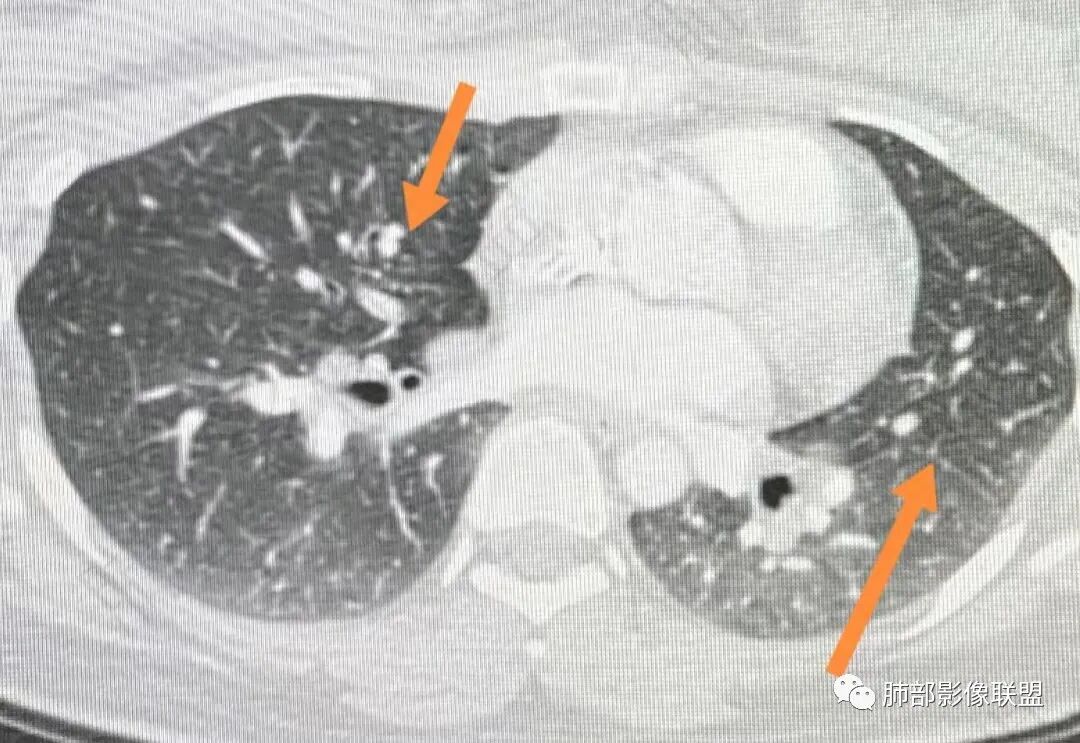

2、影像特点:双肺部分区域小叶间隔增厚并串有微小结节影,叶间裂见微小结节影。纵隔、双肺门多发肿大淋巴结,密度较高,边界清楚,未见坏死及钙化。

3、病例小结:年轻女性,无临床表现。纵隔、双肺门多发淋巴结增大(尤其双肺门淋巴结对称性增大)+叶间裂结节+小叶间隔结节,常规应想到结节病可能。

同时出现双侧肺门淋巴结肿大不符合肺癌通常转移途径。

本例需要鉴别淋巴瘤,但是淋巴瘤更多成块,密度偏低,块影中可见血管穿行,多无双肺门对称性淋巴结肿大。